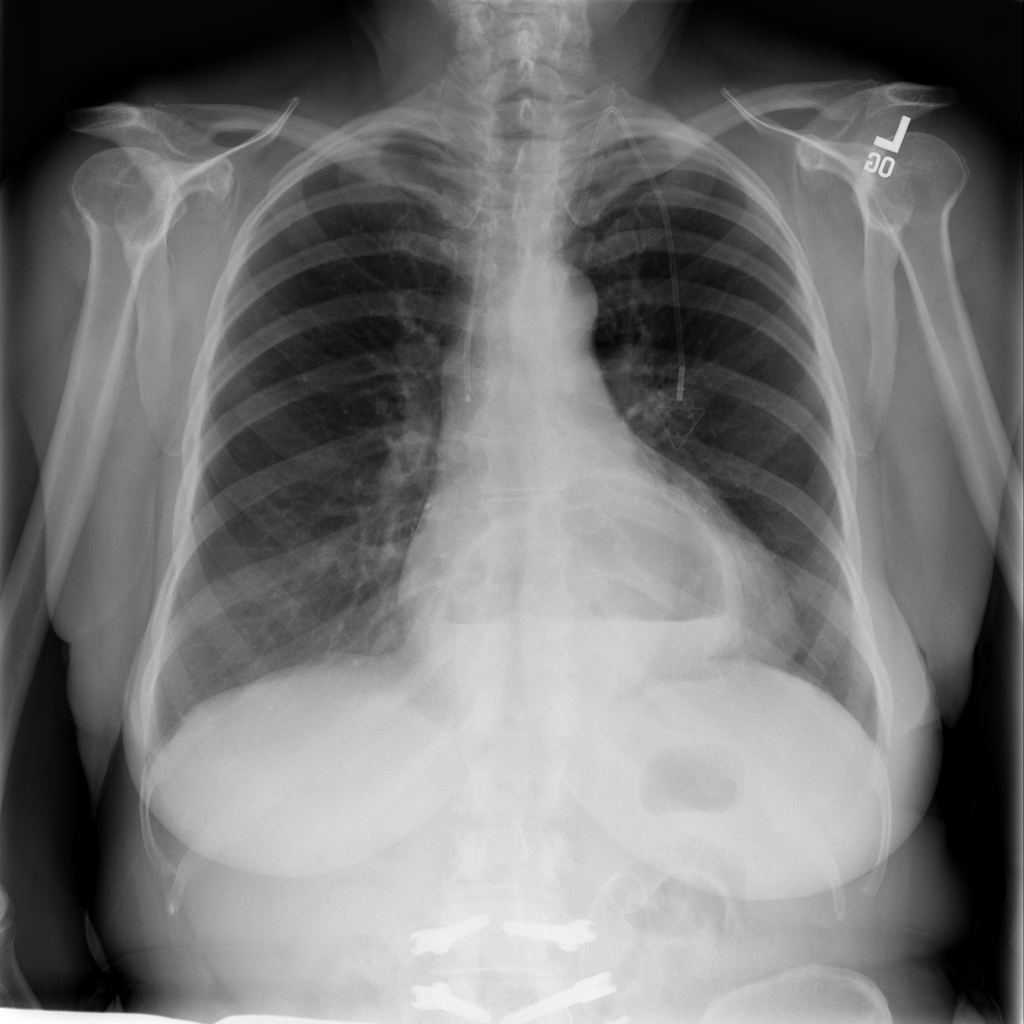

PAT-C048 · IMG-000Hernia

PAT-C048 · IMG-000

PA